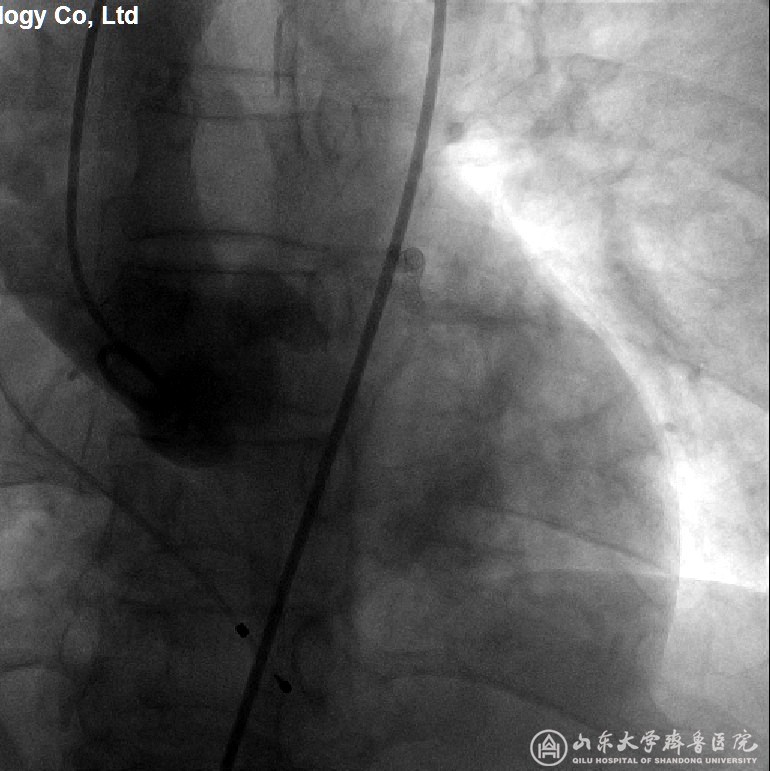

图2 (患者3)主动脉根部造影,显示主动脉瓣窦底平面及冠状动脉